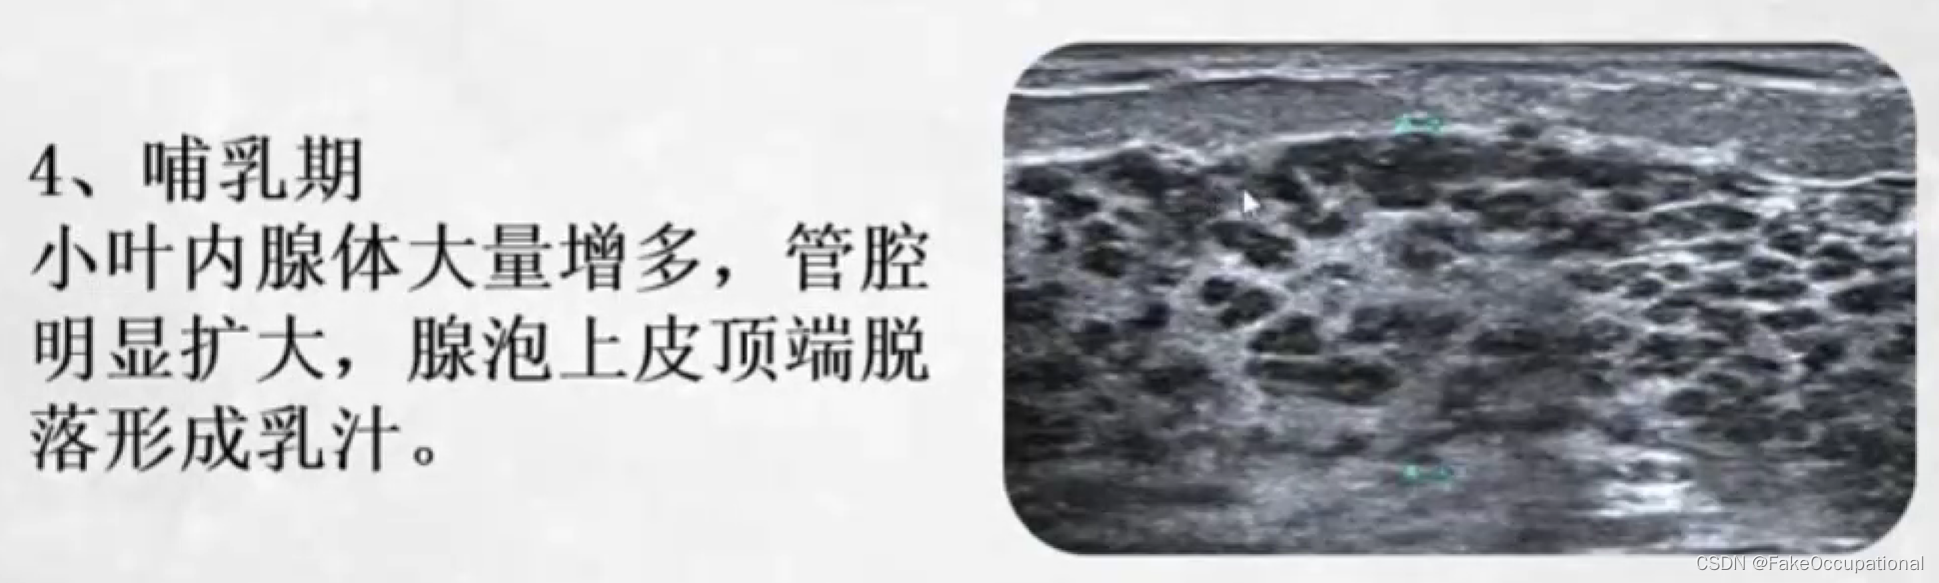

乳腺的生理解剖概要

乳腺的生理解剖概要